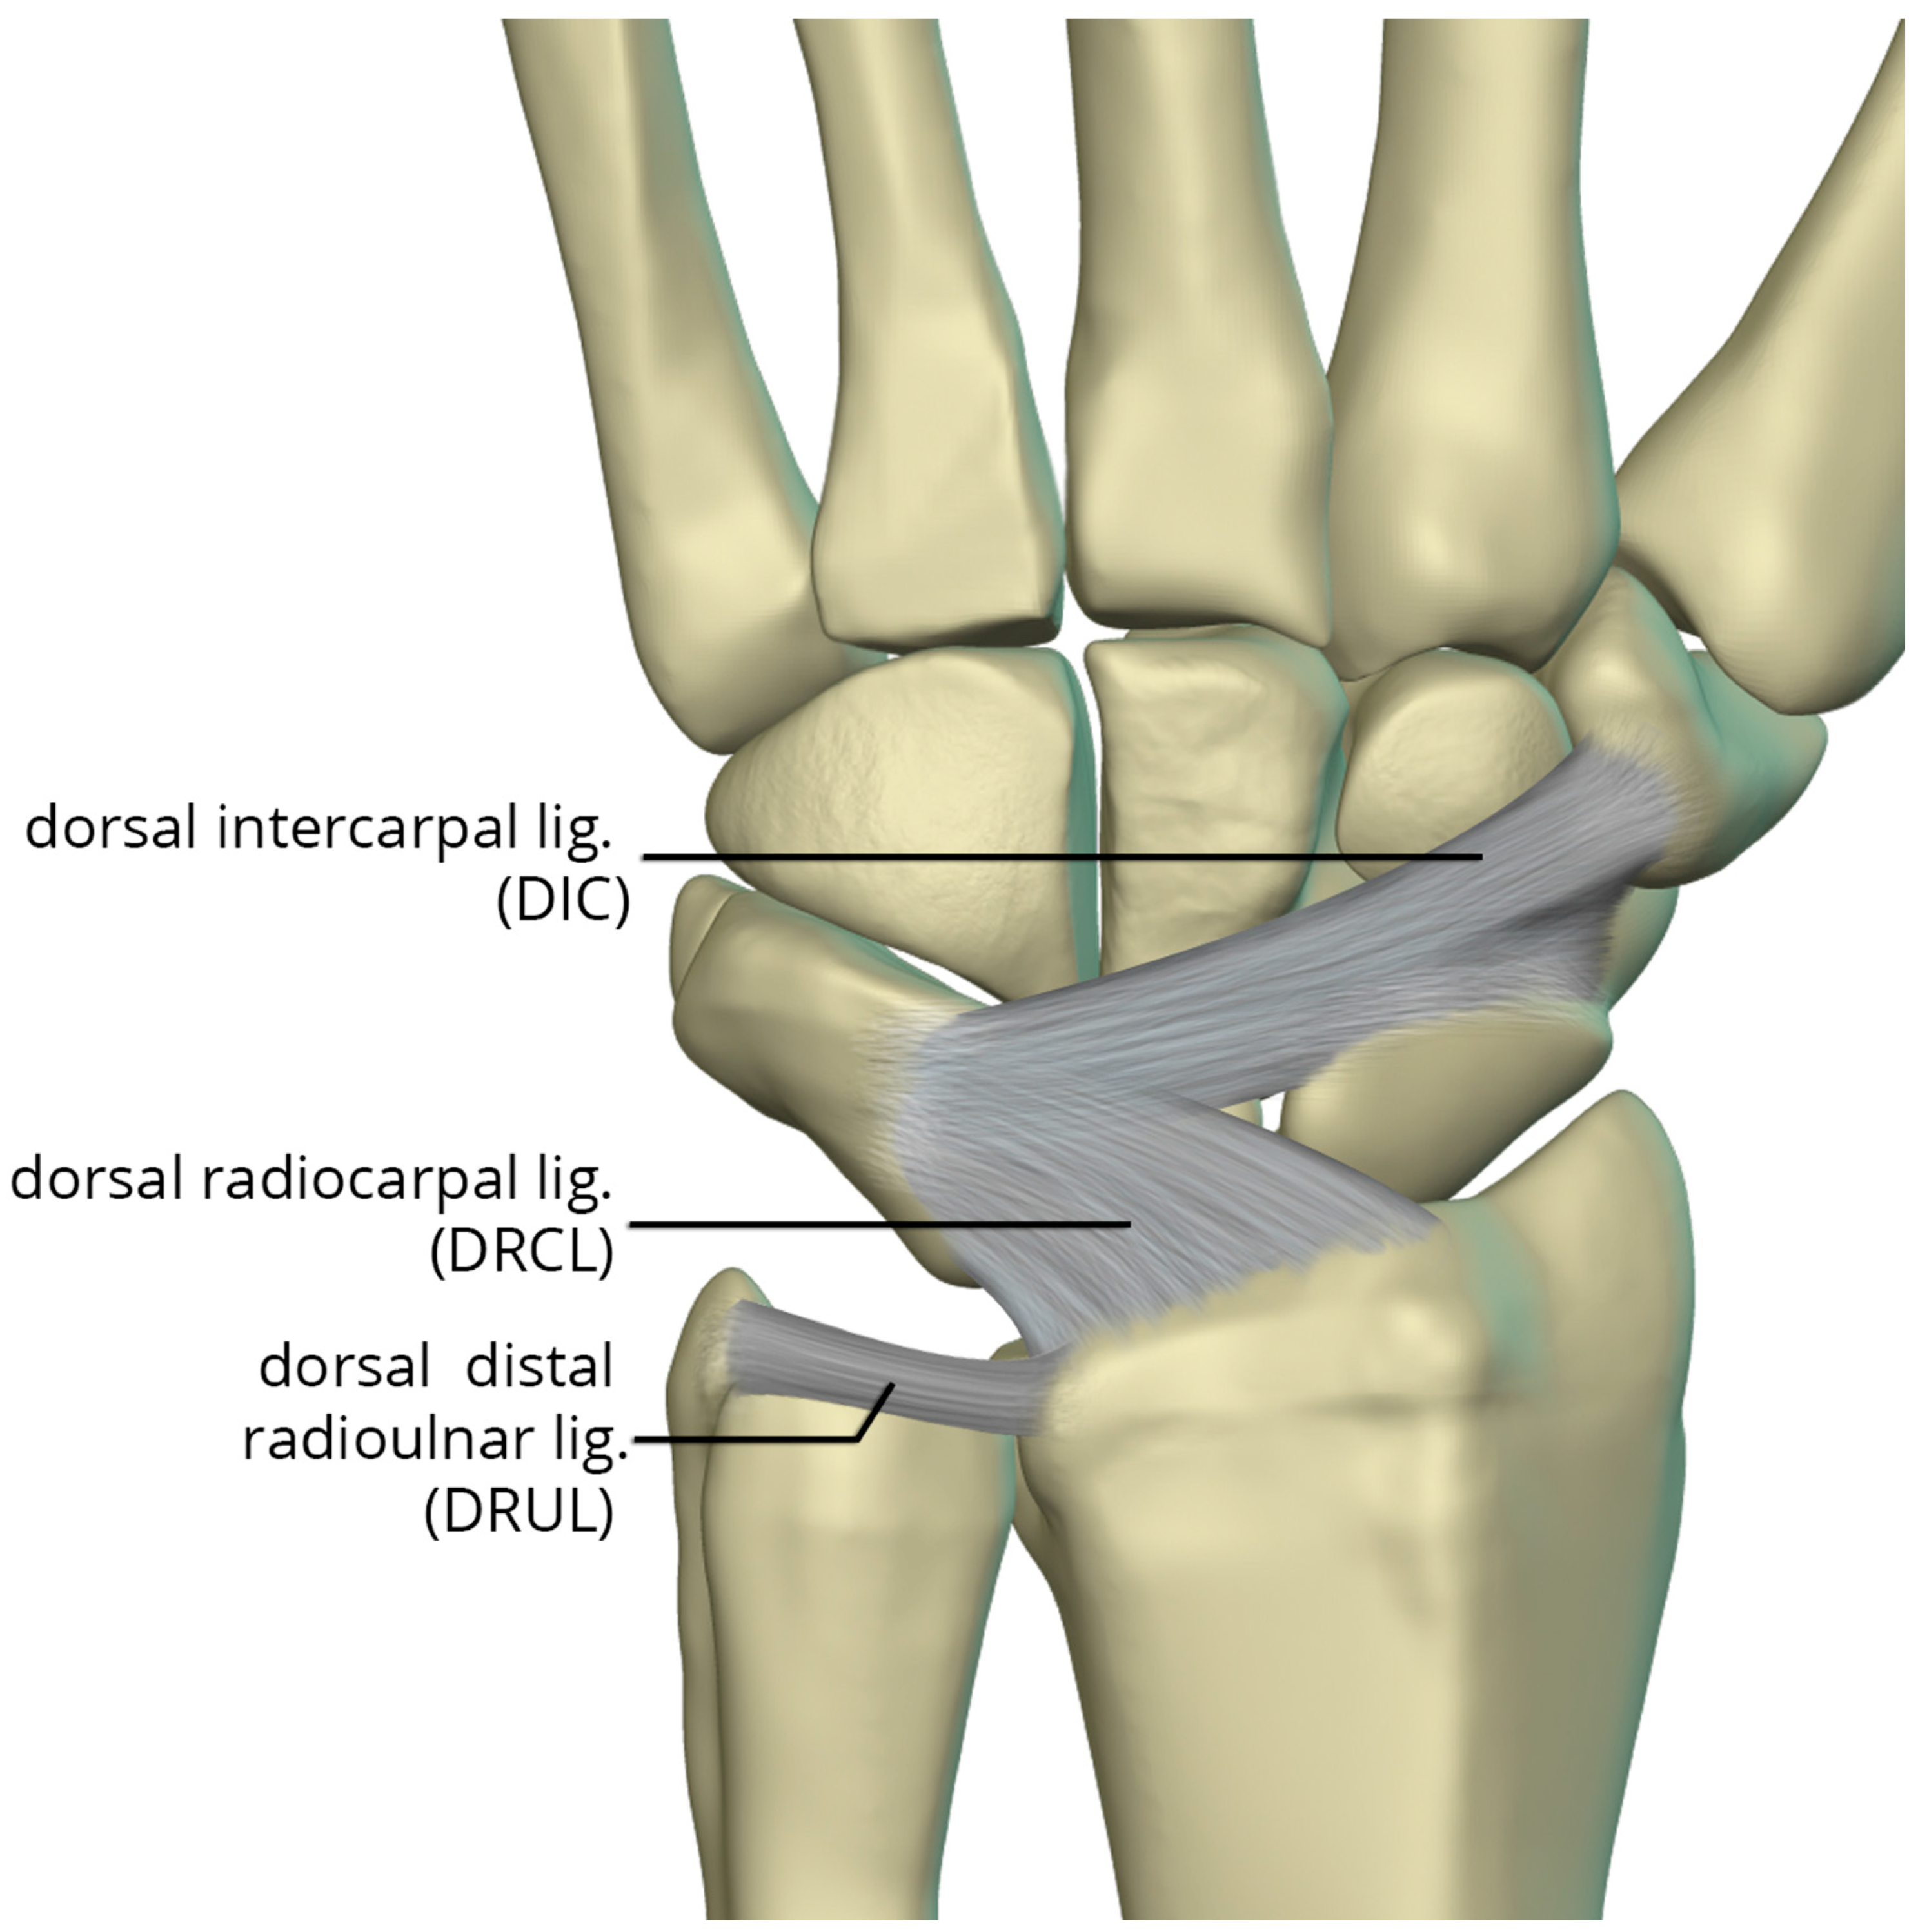

Figure 25. Illustration of the dorsal capsular ligaments: the dorsal radiocarpal ligament and dorsal intercarpal ligament.

The dorsal capsular ligaments (Figure 25) include the dorsal radiocarpal ligament (DRCL) and dorsal intercarpal ligament (DIC). The dorsal radiocarpal ligament (DRCL) is also referred to as the dorsal radiotriquetral ligament [26]. The DRCL extends from the dorsal rim of the radius, between Lister tubercle and the sigmoid notch, to the dorsal triquetrum. This ligament has fibers continuous with the fourth and fifth extensor compartment septa. Variants of this ligament include various additional bands, one of which may cover the dorsal aspect of the proximal scaphoid. The dorsal intercarpal ligament (DIC) is also sometimes referred to as the dorsal scaphotriquetral ligament due to its attachments. The DIC ligament extends from the dorsal ridge of the triquetrum to the dorsal groove of the scaphoid and proximal rim of the dorsal aspect of the trapezium. Along its course some fibers attach to the dorsal distal lunate. The DIC ligament may have one or two distinct fascicles, and sporadically has fibers extending to the trapezoid and capitate.